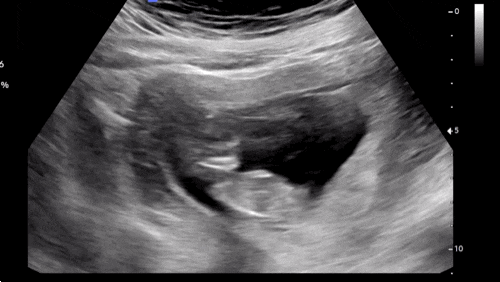

[임신 12주차]증상,드디어 첫 정밀초음파, 성별❣️

엘디와 함께한지 벌써 12주 째! 안정기 시작으로 불리우는 주수이고 나는 드디어!!! 크녹산과 이별했다~~~ ...